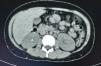

En la tomografía computada de tórax y abdomen se observaron conglomerados ganglionares en mediastino, mesenterio, retroperitoneo y región inguinal, infiltrado micronodular difuso bilateral, hepatomegalia, esplenomegalia, así como litiasis renal derecha (fig. 3).